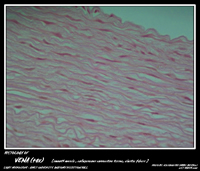

MBBS Batch 12 Histology MicroPhoto Archive

BLOOD VESSEL